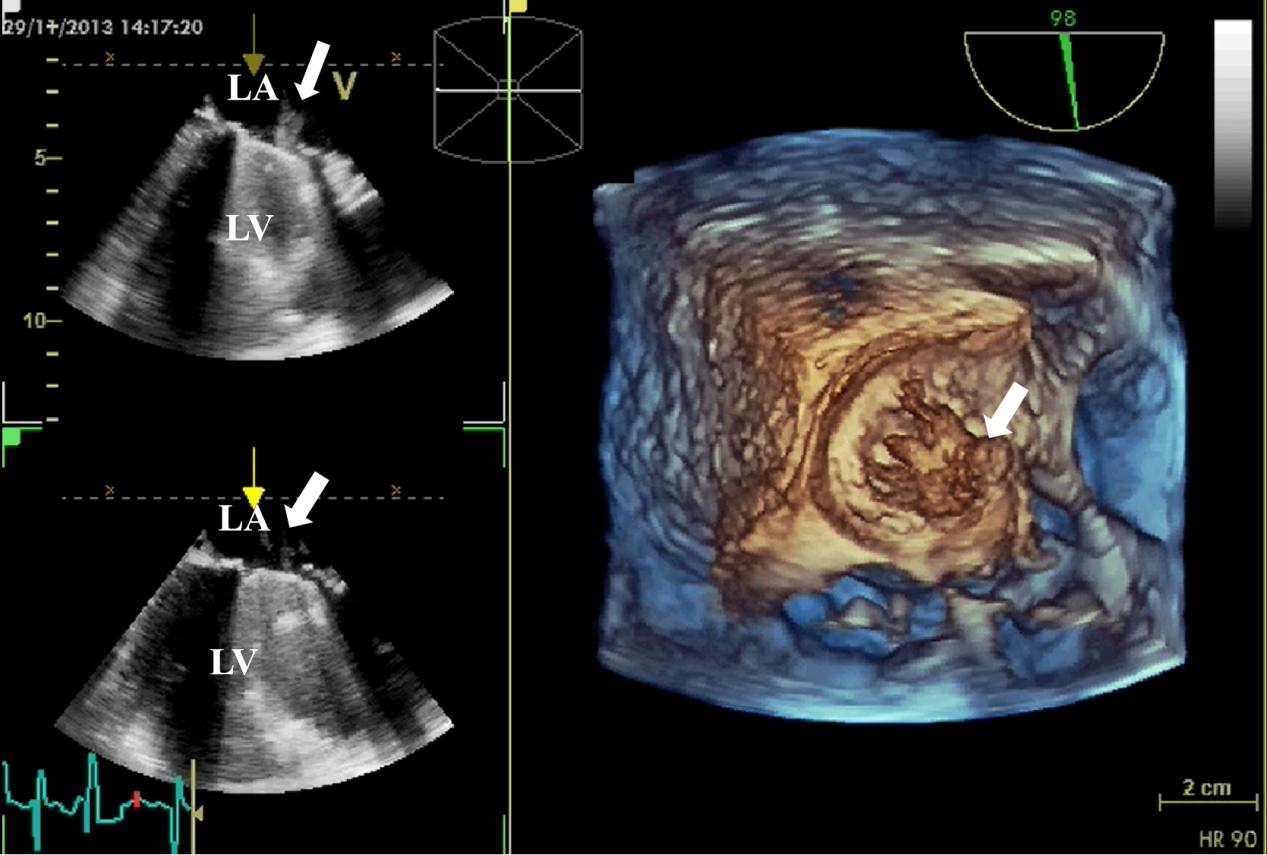

Echocardiography is the preferred imaging diagnostic modality for PVE, which can effectively identify valvular lesions and peri-valvular complications, such as abscesses, dehiscence, and paravalvular infections (Figs. 5,6,7). In the early postoperative period, attention should be paid to possible anatomical variations, such as edema-related changes, which may mimic pathological findings [23]. TEE is superior to TTE in terms of sensitivity (91% vs 65%), and its advantage mainly lies in being less susceptible to the interference of prosthetic valve artifacts. Among patients with suspected PVE, the NPV of TTE and TEE were both relatively high, ranging from 86% to 94% [9]. Furthermore, compared with two-dimensional (2D) TEE, 3D TEE can provide more comprehensive images of cardiac structures and has higher diagnostic value in the analysis of valvular lesions [46].

Fig. 5. 3D TEE detection of mechanical valve vegetation. 3D TEE indicates the formation of vegetation (white arrow) on the mechanical valve of the mitral valve. (Left) The 2D views show vegetation on the surface of the mechanical valve. (Right) The 3D view shows the formation of vegetation on the mechanical valve. 3D, three-dimensional; 2D, two-dimensional; TEE, transesophageal echocardiography; LA, left atrium; LV, left ventricle.